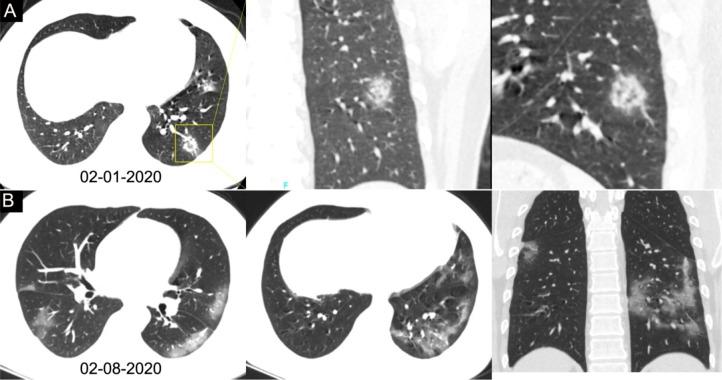

Background Chest CT is used in the diagnosis of coronavirus disease 2019 (COVID-19) and is an important complement to reverse-transcription polymerase chain reaction (RT-PCR) tests. Purpose To investigate the diagnostic value and consistency of chest CT as compared with RT-PCR assay in COVID-19. Materials and Methods This study included 1014 patients in Wuhan, China, who underwent both chest CT and RT-PCR tests between January 6 and February 6, 2020. With use of RT-PCR as the reference standard, the performance of chest CT in the diagnosis of COVID-19 was assessed. In addition, for patients with multiple RT-PCR assays, the dynamic conversion of RT-PCR results (negative to positive, positive to negative) was analyzed as compared with serial chest CT scans for those with a time interval between RT-PCR tests of 4 days or more. Results Of the 1014 patients, 601 of 1014 (59%) had positive RT-PCR results and 888 of 1014 (88%) had positive chest CT scans. The sensitivity of chest CT in suggesting COVID-19 was 97% (95% confidence interval: 95%, 98%; 580 of 601 patients) based on positive RT-PCR results. In the 413 patients with negative RT-PCR results, 308 of 413 (75%) had positive chest CT findings. Of those 308 patients, 48% (103 of 308) were considered as highly likely cases and 33% (103 of 308) as probable cases. At analysis of serial RT-PCR assays and CT scans, the mean interval between the initial negative to positive RT-PCR results was 5.1 days ± 1.5; the mean interval between initial positive to subsequent negative RT-PCR results was 6.9 days ± 2.3. Of the 1014 patients, 60% (34 of 57) to 93% (14 of 15) had initial positive CT scans consistent with COVID-19 before (or parallel to) the initial positive RT-PCR results. Twenty-four of 57 patients (42%) showed improvement on follow-up chest CT scans before the RT-PCR results turned negative. Conclusion Chest CT has a high sensitivity for diagnosis of coronavirus disease 2019 (COVID-19). Chest CT may be considered as a primary tool for the current COVID-19 detection in epidemic areas. © RSNA, 2020 ترجمه چکیده این مقاله به فارسی، در ضمیمه موجود است.

背景 胸部 CT 用于 2019 年冠状病毒病(COVID-19)的诊断,是逆转录聚合酶链反应(RT-PCR)检测的重要补充。目的 探讨胸部 CT 与 RT-PCR 检测在 COVID-19 诊断中的诊断价值和一致性。材料与方法 本研究纳入 2020 年 1 月 6 日至 2 月 6 日期间在中国武汉接受胸部 CT 和 RT-PCR 检测的 1014 例患者。以 RT-PCR 为参考标准,评估胸部 CT 对 COVID-19 的诊断性能。此外,对于多次 RT-PCR 检测的患者,分析 RT-PCR 结果(从阴性转为阳性,从阳性转为阴性)的动态转换与 RT-PCR 检测间隔为 4 天或更长时间的系列胸部 CT 扫描的一致性。结果 1014 例患者中,601 例(60%)的 RT-PCR 检测结果为阳性,888 例(88%)的胸部 CT 扫描结果为阳性。基于阳性 RT-PCR 检测结果,胸部 CT 提示 COVID-19 的敏感度为 97%(95%置信区间:95%,98%;601 例患者中的 580 例)。在 413 例 RT-PCR 检测结果为阴性的患者中,308 例(75%)的胸部 CT 检查结果为阳性。在这 308 例患者中,48%(308 例中的 103 例)被认为是高度疑似病例,33%(308 例中的 103 例)为可能病例。在对系列 RT-PCR 检测和 CT 扫描的分析中,初始阴性到阳性 RT-PCR 结果之间的平均间隔为 5.1 天±1.5;初始阳性到随后的阴性 RT-PCR 结果之间的平均间隔为 6.9 天±2.3。在 1014 例患者中,60%(57 例中的 34 例)至 93%(15 例中的 14 例)在初始阳性 RT-PCR 结果之前(或同时)有与 COVID-19 一致的初始阳性 CT 扫描。在 RT-PCR 结果转为阴性之前,24 例(42%)患者的随访胸部 CT 扫描显示改善。结论 胸部 CT 对 2019 年冠状病毒病(COVID-19)的诊断具有较高的敏感度。胸部 CT 可作为当前 COVID-19 检测在疫区的主要工具。 ©RSNA,2020